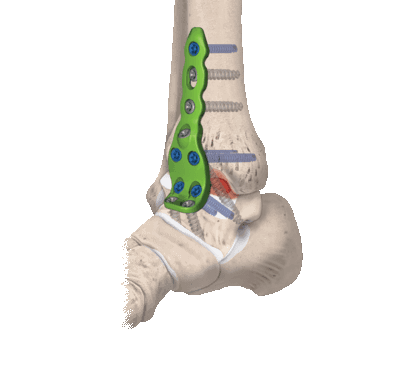

В данном случае применяются все виды оперативного лечения, но наиболее актуален внутрисуставной метод. Популярен артродез голеностопного сустава пластиной, при котором облегчается установка угла между большеберцовой костью и голенью.

- Разрез мягких тканей оптимален на передней или внутренней поверхности сустава;

- Получив доступ к хрящевым поверхностям - они удаляются вместе с поражёнными элементами костной ткани;

- Между костями располагаются трансплантаты, которые прочно фиксируются;

- Между голенью и стопой формируют угол 90°;

- Накладываются швы и гипсовая повязка.

В гипсе придётся проходить 6-9 месяцев в зависимости от рекомендаций врача, затем назначается курс лечебной гимнастики для частичной иммобилизации оперированной конечности. Артродез голеностопного сустава обеспечивает полную его неподвижность на всю жизнь.